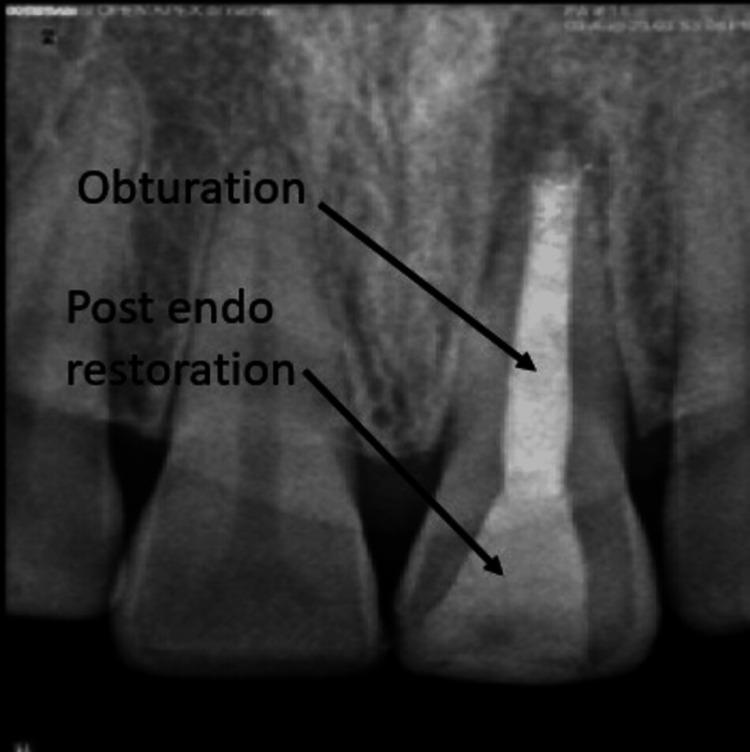

Apexification is a crucial procedure for achieving apical healing in non-vital teeth with open apices. Traditionally, calcium hydroxide has been used for this purpose, but it has significant drawbacks, including prolonged treatment duration, increased risk of root fracture, and the potential for porous barrier formation. Mineral trioxide aggregate (MTA) has emerged as a superior alternative due to its biocompatibility, faster setting time, and better sealing properties. However, MTA extrusion into periradicular tissues can cause persistent discomfort. The use of an internal matrix such as platelet-rich fibrin (PRF) can help contain MTA within the root canal, enhancing treatment outcomes. A 35-year-old female presented with dull, aching pain in tooth 21, a history of trauma 10 years prior, and incomplete root canal therapy 2 years ago. Diagnosis revealed an open apex with chronic apical periodontitis and pulpal necrosis. Initial management involved canal disinfection with sodium hypochlorite (NaOCl) and calcium hydroxide as intracanal medication. One week later, the patient returned asymptomatic. PRF was prepared from the patient's blood and used as an internal matrix. Mineral trioxide aggregate was then placed against the PRF membrane to form an apical stop. The canal was subsequently obturated with thermoplasticized gutta-percha and restored with composite resin. The use of PRF and MTA provided effective apical sealing, preventing material extrusion and promoting tissue healing. The PRF matrix facilitated the controlled placement of MTA, minimizing complications and enhancing periapical healing. The combination of PRF as an internal matrix and MTA for apical barrier formation represents a promising approach for managing non-vital teeth with open apices. This technique ensures better control over material placement, reduces treatment time, and improves the overall success of endodontic therapy. The aim of this case report is to describe the endodontic management of a non-vital permanent tooth with an open apex and chronic apical periodontitis using a single-step apical barrier technique with MTA and PRF as an internal matrix.

根尖诱导成形术是使根尖孔开放的无髓牙实现根尖愈合的关键步骤。传统上,氢氧化钙一直用于此目的,但它有显著缺点,包括治疗时间延长、根折风险增加以及形成多孔屏障的可能性。由于其生物相容性、更快的凝固时间和更好的封闭性能,矿物三氧化物凝聚体(MTA)已成为一种更优的替代材料。然而,MTA挤出到根尖周组织中会导致持续不适。使用富含血小板纤维蛋白(PRF)等内部基质有助于将MTA限制在根管内,提高治疗效果。一名35岁女性,主诉21号牙钝痛、隐痛,10年前有外伤史,2年前根管治疗未完成。诊断显示根尖孔开放伴慢性根尖周炎和牙髓坏死。初始治疗包括用次氯酸钠(NaOCl)和氢氧化钙进行根管消毒并作为根管内用药。一周后,患者复诊时无症状。从患者血液中制备PRF并用作内部基质。然后将矿物三氧化物凝聚体放置在PRF膜上以形成根尖屏障。随后用热塑牙胶充填根管并用复合树脂修复。PRF和MTA的使用提供了有效的根尖封闭,防止材料挤出并促进组织愈合。PRF基质有助于MTA的可控放置,将并发症降至最低并促进根尖周愈合。PRF作为内部基质与MTA联合用于根尖屏障形成是处理根尖孔开放的无髓牙的一种有前景的方法。该技术可更好地控制材料放置,缩短治疗时间并提高根管治疗的总体成功率。本病例报告的目的是描述使用以MTA和PRF作为内部基质的单步根尖屏障技术对一颗根尖孔开放且患有慢性根尖周炎的无髓恒牙进行根管治疗的情况。